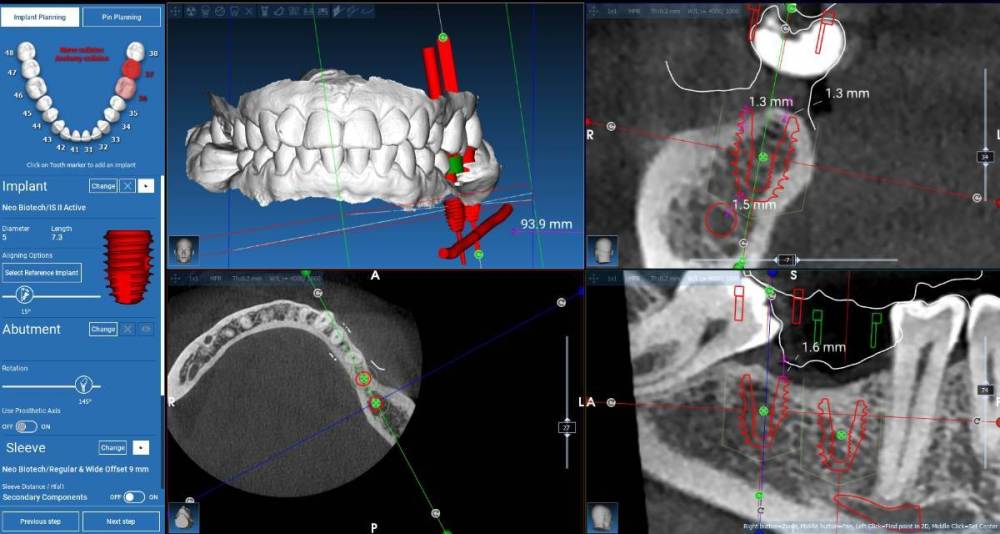

stommm Опубликовано 23 августа, 2023 Поделиться Опубликовано 23 августа, 2023 Попробуйте вестибулярнее нарисовать и поставить. проще с с десной потом работать будет.в области нижних 7 особенно актуально. Несколько таких кецсов с проблемами. Вестибулярно все супер, а язычно нарастить не удаётся или плохо удаётся. Язык давит Ссылка на комментарий

Fin Опубликовано 23 августа, 2023 Автор Поделиться Опубликовано 23 августа, 2023 5 часов назад, stommm сказал: Попробуйте вестибулярнее нарисовать и поставить. проще с с десной потом работать будет.в области нижних 7 особенно актуально. Несколько таких кецсов с проблемами. Вестибулярно все супер, а язычно нарастить не удаётся или плохо удаётся. Язык давит Имеете ввиду так? Всю кератинизированную слизистую придется смещать язычно. СДТ с апикальном смещением вестибулярно. Ссылка на комментарий